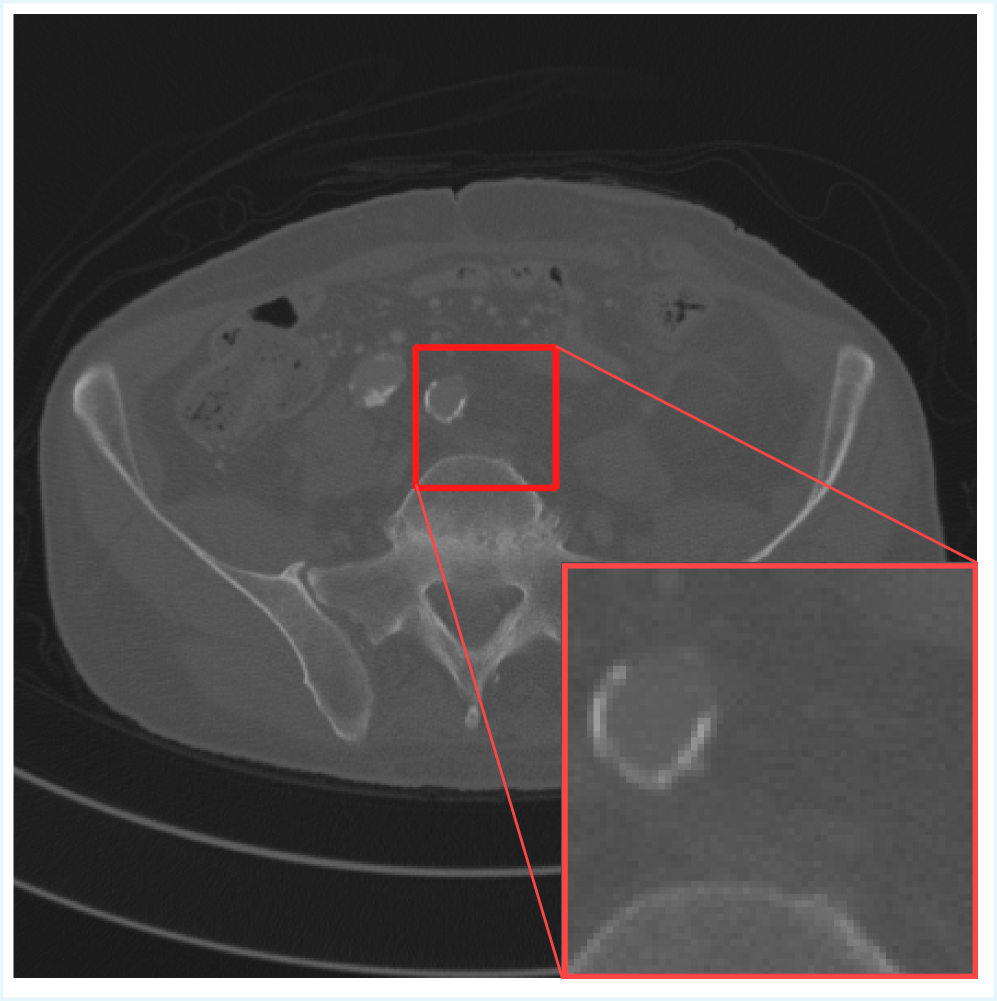

This process yielded a total of 16,628 spatially aligned pairs of LDCT and NDCT slices. This pre-processing ensures consistency and comparability across experiments, allowing reliable assessment of image enhancement performance. An illustrative example of the dataset is shown in Figure 1.

Figure 1: Images (a) and (b) show full 512×512512\times 512 CT slices for LDCT and NDCT, respectively, with a highlighted 96×9696\times 96 region indicated by the red box.